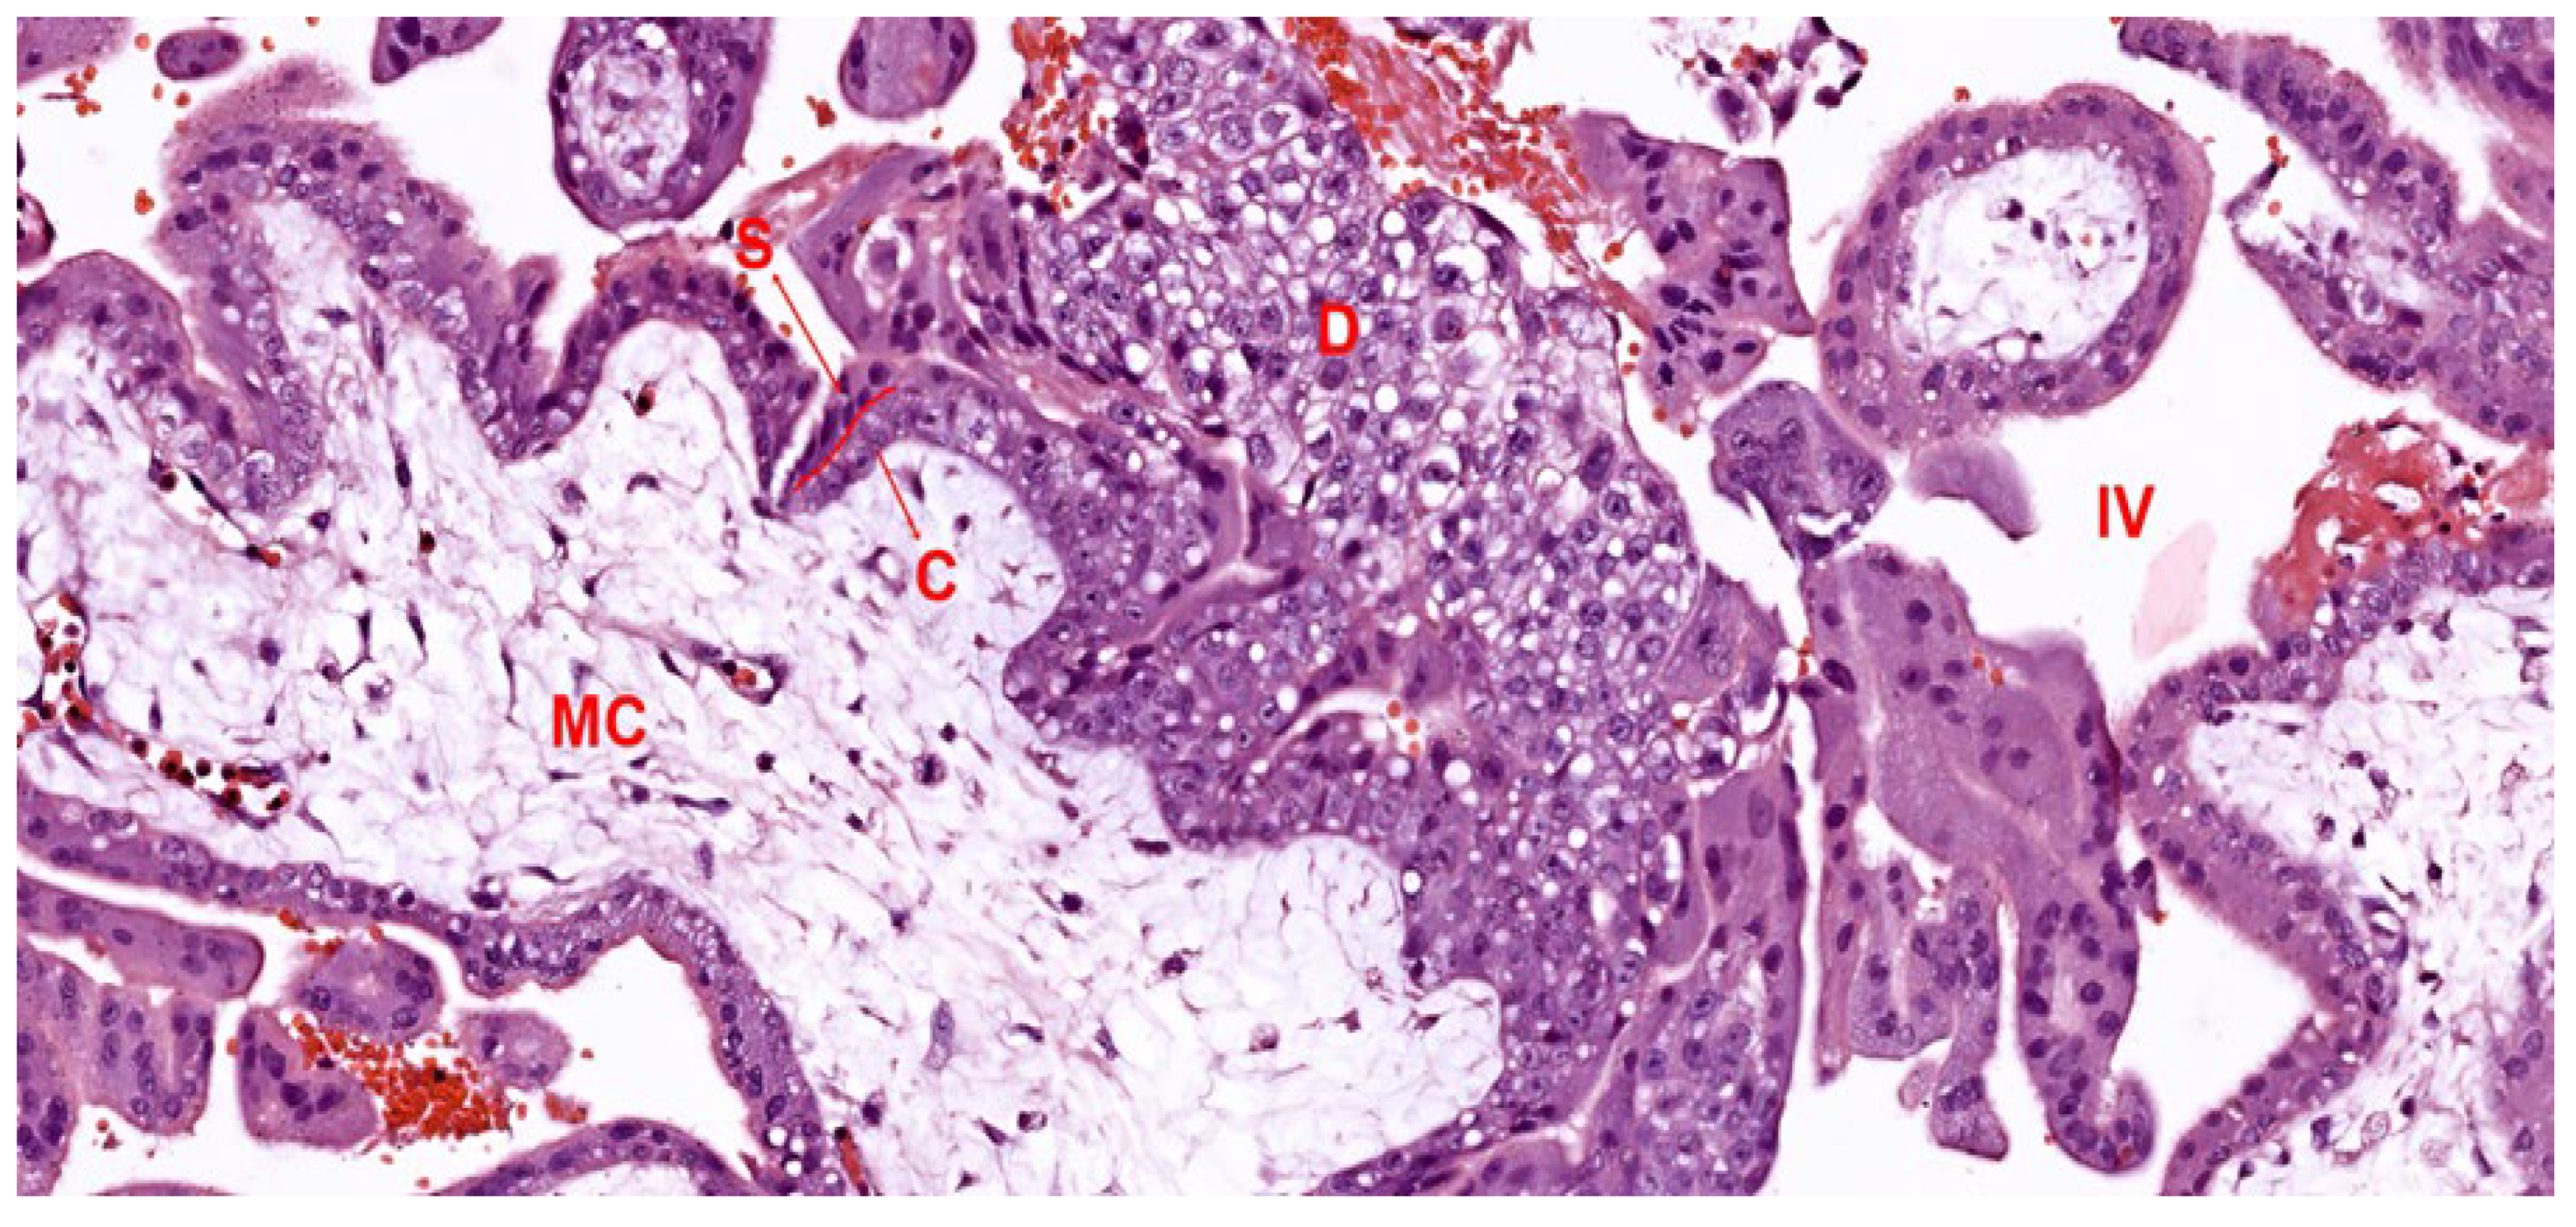

2.2. Development of the Villous Tree

2.2.1. Mesenchymal Villi

2.2.2. Immature Intermediate Villi

2.2.3. Stem Villi

2.2.4. Mature Intermediate Villi

2.2.5. Terminal Villi

| Villous Type | Timing | When Maximum | % Volume at Term | Size | Characteristic Features | Primary Function |

|---|---|---|---|---|---|---|

| Mesenchymal Villi [56] | 5 weeks–term | 0 to 8 weeks | <1% | 120–250 μm (<8 weeks), 60–100 μm (>8 weeks) | Primitive stroma, thick trophoblastic cover, few fetal vessels | Proliferation and growth precursor for other villous types |

| Immature Intermediate Villi [50] | 8 weeks–term, peaks 14–20 weeks | 14 to 20 weeks | 5–10% | 100–200 μm, up to 400 μm | Reticular stroma with fluid-filled channels, visible Hofbauer cells, limited vascularization | Growth centers for villous tree development and branching |

| Stem Villi [57] | 8 weeks–term | Term | 20–25% | 150–300 μm | Fibrotic stroma, large vessels with media and adventitia, primary structural support | Provides structural support as the ‘trunk’ of a villous tree, minimal exchange |

| Mature Intermediate Villi [58] | Third trimester | Third trimester | 25% | 80–150 μm | Loose, unoriented connective tissue fibers, capillary-rich with vascular lumens < 50% | Significant role in exchange, structural support for terminal villi formation |

| Terminal Villi [3] | Third trimester | Term | 40–50% | 60 μm | High capillary density (>50% vascular lumen), thin trophoblastic cover, main exchange site | Primary site of feto-maternal exchange due to high capillary volume and efficiency |